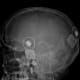

In January 2020, I led the surgical team in the cochlear implant procedure, placing a receiver-stimulator under the skin behind her right ear and inserting an array of 22 electrodes into the cochlea, carefully opened by microscopic drilling of the mastoid bone. After a month of healing, the patient met with one of the experienced audiologists in the USC Caruso Department of Otolaryngology to activate the device via an external sound processor. The moment it was switched on, the patient was overjoyed.